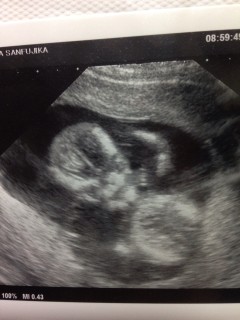

初めて心拍音を聴きました。 2週間前は3センチ半だったのに、今回は6.2センチ。 姿もとっても可愛らしい。 このまま無事に育ってね。(*^_^*)

二週間ぶり4回目の検診です。 サイズはアタマからおしりまでで5.5センチ。順調だそうで一安心^^ 左手をグーパーして、アタマをぽりぽりかいてるのが見れました!小さなおててが本当にキュート!正面からの写真でなんだか笑ってるみたいでこっちまで顔が緩みます^^

初めての経腹エコー、手足をバタバタ動かしてとても元気でした。丸まっての頭殿長は5.16cm。久々に運転をしたのでフラフラになってしまいましたが元気な姿を見ることが出来て今後が楽しみです。